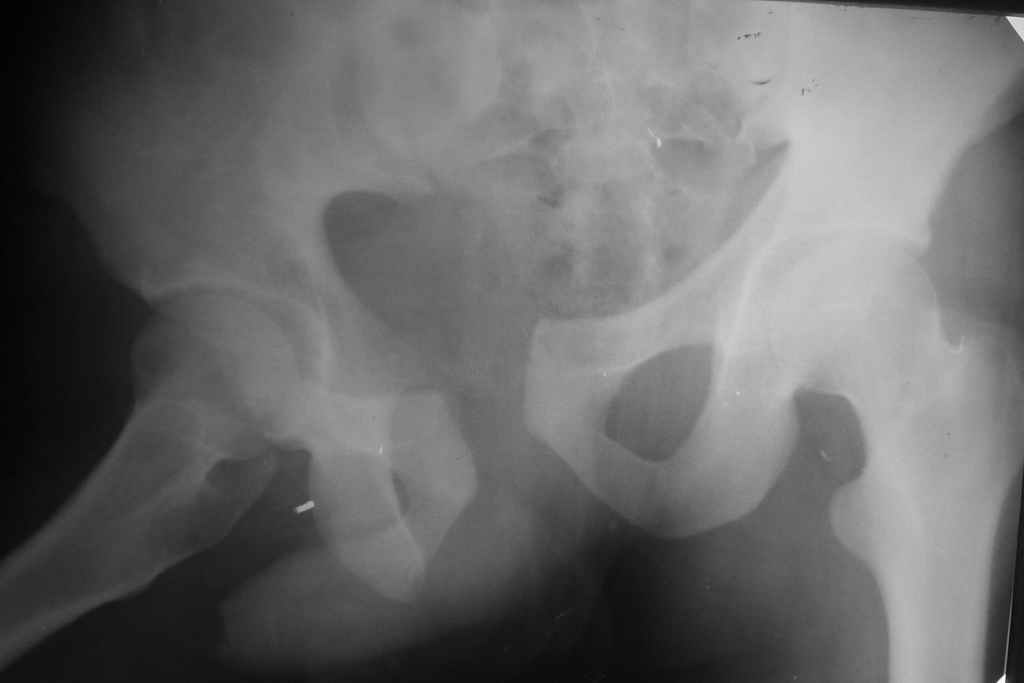

Уважаемые коллеги! На днях оперировал перелом таза месячной давности - разрыв симфиза, перелом обеих ветвей правой лонной кости, трансфораминальный перелом крестца слева. Представляю рентгенограммы с задержкой - технические причины.

Предоперационные рентген и КТ, в операционной - снимки после каждого фиксатора. Вертикальное смещение полностью устранить не удалось. В первую очередь за счет заднего полукольца. Хотя при компрессии на стержнях горизонтальное смещение было сантиметра 1,5. Т.е. крестец, на мой взгляд еще не сросся. От коллег хотел-бы услышать допустима-ли такая остаточная деформация?